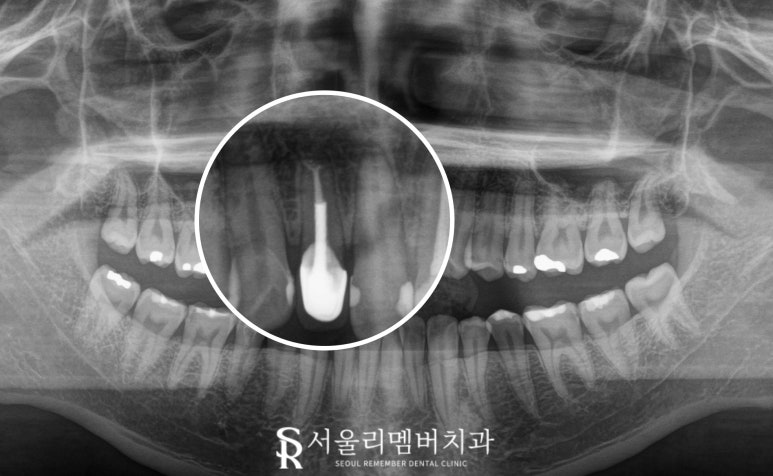

2025.06.25

앞니 부위의 치근단 절제술은

심미적으로 중요한 치아를 보존하면서

만성 염증을 근본적으로 해결할 수 있는

치료법입니다.